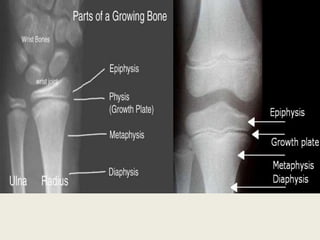

A typical long bone consists of :

- Epiphysis

distal to the physis

(growth plate )

-Metaphysis

on the opposite side

of the physis from the epiphysis

-Diaphysis

is the long shaft beyond

the metaphysis

physealanatomy

• The growth plate (physis) is translucent ,

cartilaginous disk separating the epiphysis

from the metaphysis .

and is responsible for longitudinal growth of

long bones